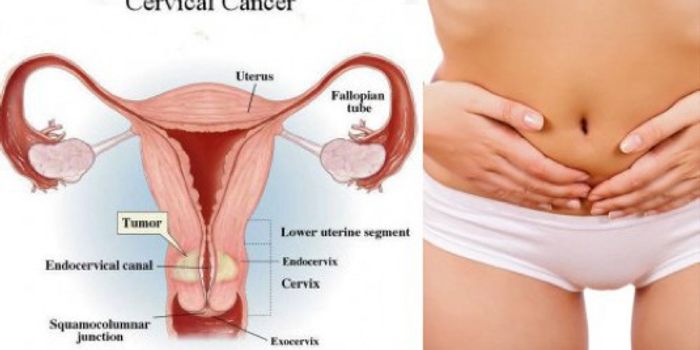

JUN 01, 2016CancerInvasive cervical cancer will be diagnosed in nearly 13,000 American women this year. Although routine Pap screening has ...